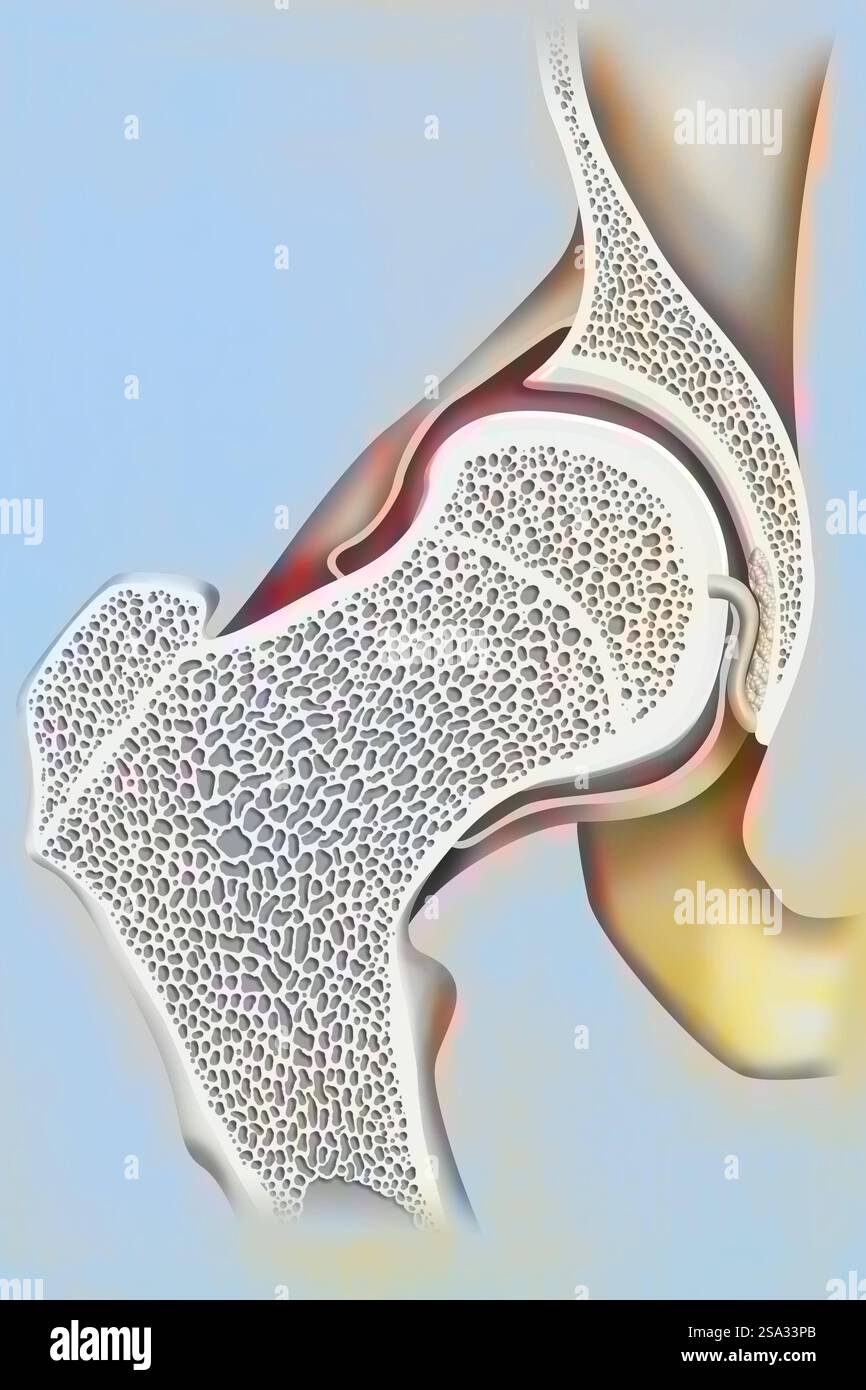

Coxofemoral joint and femoral neck. Hip drawing 016238 052 Stock Photohttps://www.alamy.com/image-license-details/?v=1https://www.alamy.com/coxofemoral-joint-and-femoral-neck-hip-drawing-016238-052-image642999011.html

Coxofemoral joint and femoral neck. Hip drawing 016238 052 Stock Photohttps://www.alamy.com/image-license-details/?v=1https://www.alamy.com/coxofemoral-joint-and-femoral-neck-hip-drawing-016238-052-image642999011.htmlRM2SA33PB–Coxofemoral joint and femoral neck. Hip drawing 016238 052